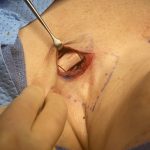

Plastic Surgery Case Study – Reductive Shoulder Reshaping Combined With Rib Removal Waistline Narrowing Surgery

Background: Shoulder narrowing surgery is done in either transgender male to females or cis-females for shoulder dysphoria. Having done many such procedures at this point I have had the epiphany that the term ‘shoulder narrowing’ does not accurately describe what occurs. Because the clavicle is a lazy s-shaped bone with a horizontal orientation, a removal Read More…